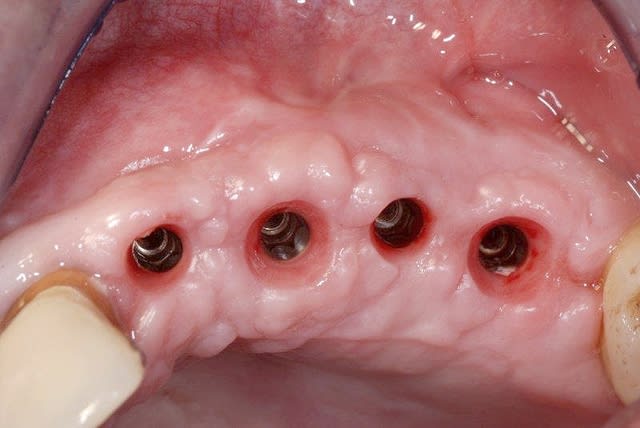

27/11/2010 à 23h35

ça sent la fin

la 24 aurait mérité un pilier de cicat plus évasé.

Vis cicat m6hyqf - Eugenol

Pick up z6jmtt - Eugenol

Aspect gingival s6chqt - Eugenol

quelques petites questions à toi growler...sur ces superline (c'en est bien non?)

tes vis de cicat, tu les réutilises? (après sté of course)

et pour les transferts d'empreinte (pick up ou pop up ) tu utilises les différents modèles avec les tailles d'émergence différente ou toujours les mêmes (et si oui les quels?)

oui je réutilise les piliers de cicat qui sont de très bonne qualité de finition. Un coup de bac à ultrason et sté.

les transferts: en pick-up j'utilise surtout les courts et je vais passer commmande de quelques transferts dont les émergences reproduisent celles des divers piliers de cicat à disposition. Ainsi, l'empreinte reproduit l'émergence sans qu'il soit nécessaire d'injecter du matériau d'empreinte dans cette zone qui ne reste pas longtemps stable dès que le pilier de cicat est retiré. (c'est finalement ce qu'on fait en personnalisant un transfert avec du compo pour empreinter une émergence réalisée avec une provisoire anatomique)

merci, donc pour toi, les plus utiles sont les 4,5 et les 5,5 en version courte...

pareil pour les pop up?

oui

1...45